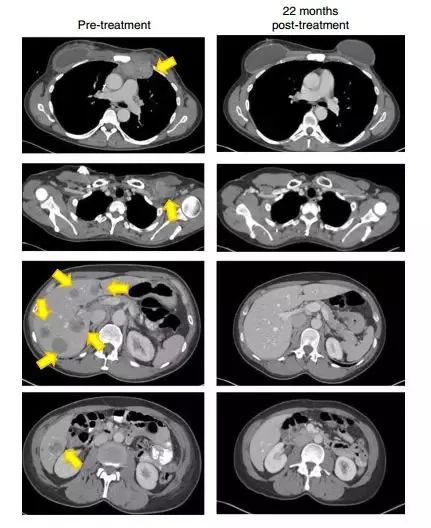

22个月后,这名患者的肿瘤(黄色箭头)消失得无影无踪(图片来源:《Nature Medicine》)